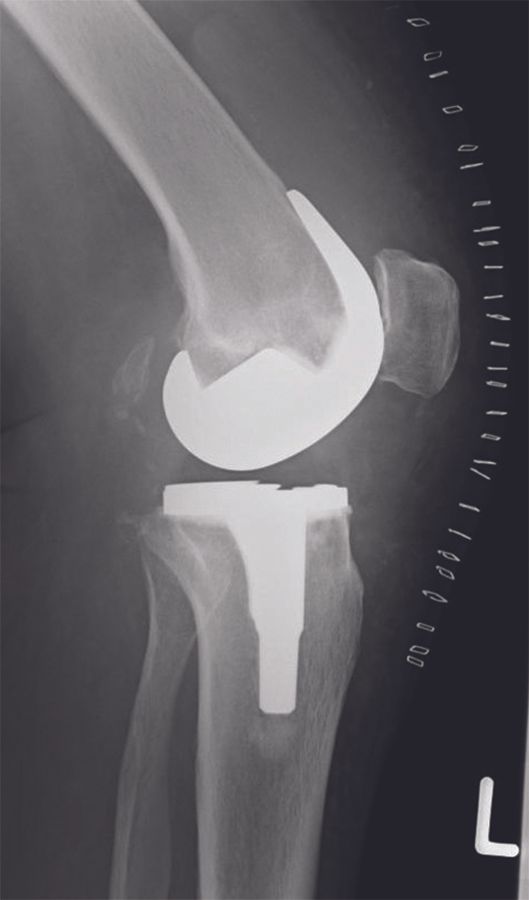

Approximately 600 patients were operated in our clinic with the balanced gap technique presented in this paper. In this patient cohort, the HKA changed from -6.7° ± 3.6° (range, -0.5 to -19°) preoperatively to -2.9° ± 2.1° (range, -0.5 to -5.5°) postoperatively. Hence, a residual varus was seen in all patients (Figures 15 - 16).

A major advantage of the Journey BCS system is that it comprises a medial inclination of 3° of the polyethylene and an asymmetric geometry of the femoral condyles; the system, therefore, allows a tibial neutral cut even when a slight varus alignment is targeted.

Working towards a more anatomical knee component alignment can be done in three different ways: adjusting the tibia only, adjusting both the tibia and the femur (as in the classical anatomical and kinematic alignment), and adjusting the femur only. However, studies have shown that deviation from neutral alignment on the tibial component should be avoided, and it is safer to have the alignment change coming from the femoral component [14,15], which is respected in our approach.